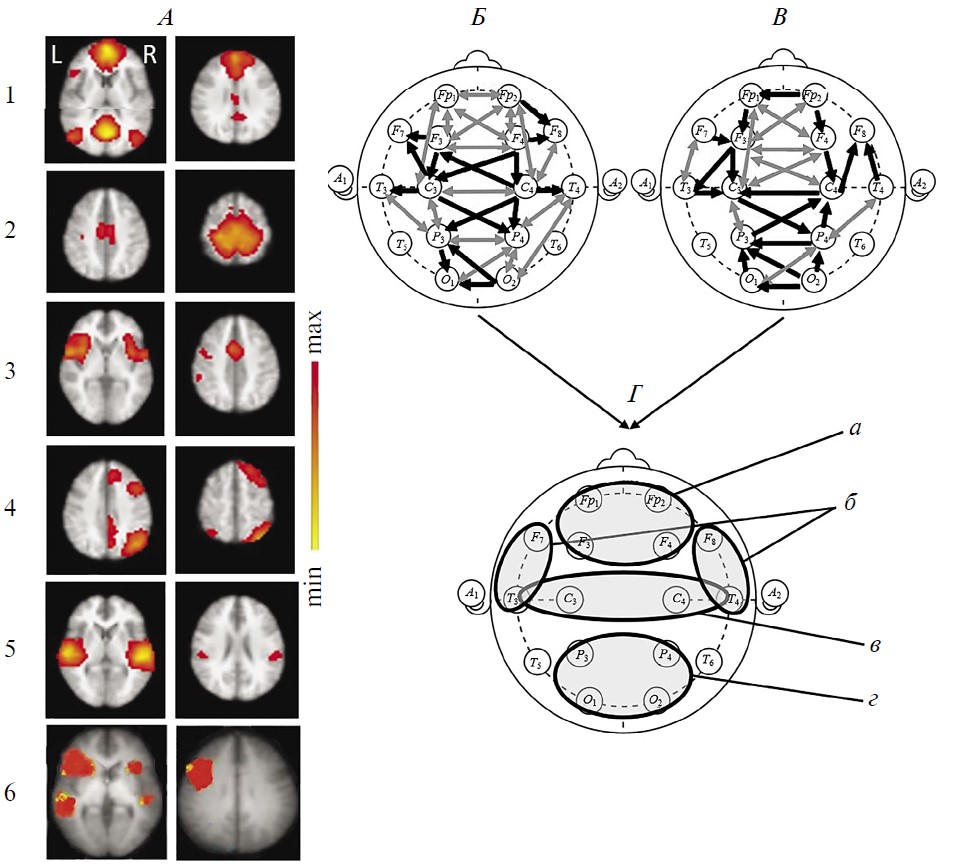

У здоровых испытуемых при групповом анализе RSN фМРТ были верифицировны все 6 сетей, указанных во введении в качестве наиболее значимых для восстановления сознания (рис. 1, А). Большинство из них (за исключением лобно-теменных) имеют симметричную билатеральную топографию, отражая наличие устойчивых межполушарных структурно-функциональных взаимодействий. В трех сетях (DMN, лобно-теменная, речевая) фокусы активности представлены как в лобных, так и в теменных (задне-височных) областях в пределах одного полушария, указывая на сохранность функционирования лобно-теменного пространства, необходимого для сознательной деятельности [1, 51, 52].

Рис. 1. Функциональные сети функциональной магнитно-резонансной томографии (фМРТ) и коннективность ЭЭГ-диапазона 1–15 Гц у здоровых испытуемых в состоянии покоя (n = 15).

А — усредненные по группе испытуемых RSN фМРТ: 1 – DMN, 2 - сенсомоторная, 3 – сеть управляющих функций (исполнительного контроля), 4 – лобно-теменная, 5 – слуховая, 6 – речевая. Шкала справа характеризует уровень максимальной интенсивности сети. Б, В — усредненная в этой же группе испытуемых коннективность ЭЭГ по корреляции Пирсона. Черные линии — однонаправленные связи, серые — двунаправленные, согласно методу причинности Грейнджера. Б — коннективности, рассчитанные на непрерывных записях, В — в режиме псевдо-ВП. Г — зоны концентрации функциональных связей ЭЭГ: а — лобные, б — височно-передневисочные, в — центральные, г — затылочно-теменные.

На рис. 1 представлены также результаты групповой оценки коннективности ЭЭГ диапазона 1–15 Гц этих испытуемых: при непрерывной записи состояния покоя (рис. 1, Б) и в режиме псевдо-ВП (рис. 1, В). На обеих схемах видно значительное число внутри- и особенно межполушарных связей, превышающих уровень корреляции Пирсона 0.5. Многие из них являются разнонаправленными (согласно методу причинности Грейнджера). Важно подчеркнуть, что паттерны связей характеризуются выраженным сходством друг с другом при обоих методах расчета коннективности. Хотя число отобранных связей несущественно меньше при расчете в режиме псевдо-ВП: 33 и 29 соответственно. Особенностью непрерывных записей ЭЭГ является также более частая встречаемость (на 7) двунаправленных связей.

Общее количество коннективностей ЭЭГ преобладает в передних корковых областях. В характере внутриполушарных связей, в первую очередь для непрерывных реализаций ЭЭГ (рис. 1, Б), можно отметить преимущественную правостороннюю направленность (по Грэйджеру) и превалирование их числа в правом полушарии, что, согласно литературным данным может рассматриваться как отражение возможно большей сопряженности этой гемисферы с ощущением своего тела [53] и самоосознанием [54].

Выделить на рис. 1 на схемах Б и В локусы топографического соответствия отдельным сетям фМРТ покоя затруднительно. Однако можно отметить несколько корковых областей, характеризующихся концентрацией функциональных связей: симметричные лобные, центральные, затылочно-теменные, а также височно-передневисочные. Топография этих локусов коннективности ЭЭГ (рис. 1, Г) совпадает с активными зонами сразу нескольких сетей фМРТ покоя: DMN, сенсомоторной, управляющих функций, слуховой и речевой. Можно полагать, что указанные области концентрации связей ЭЭГ можно рассматривать в качестве зон межсетевой коннективности, наличие которой отмечено в ряде публикаций в качестве значимой для восстановления сознания [43, 55].